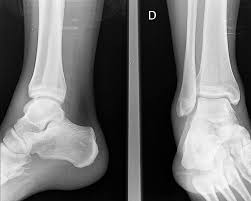

Existen muchos factores que predisponen a sufrir este tipo de lesión. Habitualmente se clasifican en: Factores intrínsecos, que hacen referencia a lo inherente a la propia naturaleza del cuerpo humano y sus funciones (factores anatómicos, propiocepción, etc.). Factores extrínsecos, aquellos…